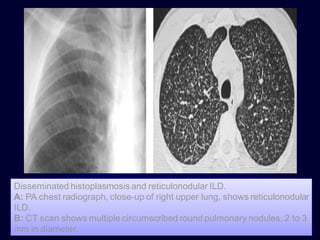

Disseminated histoplasmosis and reticulonodular ILD.

A: PA chest radiograph, close-up of right upper lung, shows reticulonodular

ILD.

B: CT scan shows multiple circumscribed round pulmonary nodules, 2 to 3

mm in diameter.